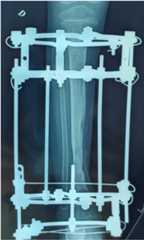

X-ray at 8 months of Ilizarov external fixator: the quality of the bone formed allows the fixator to be removed.

Fig. 6.

Fig. 7.

Frontal right tibia x-ray: bone consolidation after 10 months of treatment.

Fig. 8.

Profile x-ray of the right tibia: bone union after 10 months of treatment.